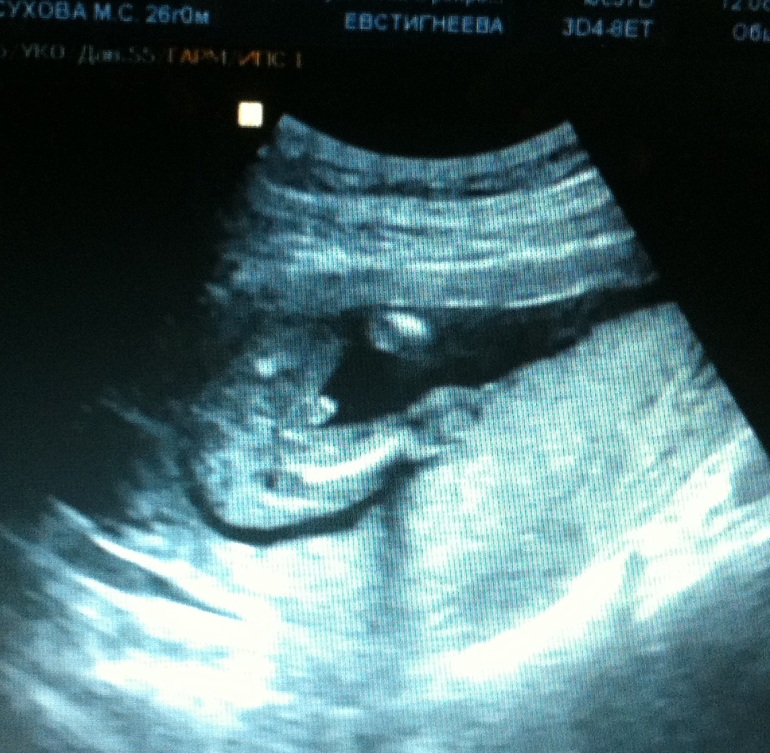

Сегодня мы с мужем и сыном от предыдущего брака поехали на платное 3D-4D УЗИ.

Всю процедуру я смотрела на экран-там дублирующий экран для мамочки)

И мы смотрели на малыша во всех ракурсах, как вдруг.......я увидела крохотный пенис со всеми прилагающимися!!!!!!!! Я чувствовала "жопой" простите , что там мальчик-но увидеть -это просто непередаваемо!

Вообщем вышли через полчаса с кучей фоток, видео и отличным настроением)